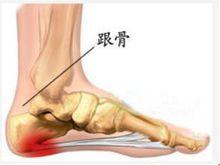

跟骨刺在醫學上稱骨贅、骨質增生。骨刺是一種正常的骨骼生理退化現象,是人體的一種保護性生理反應,每個人都難以避免,區別僅僅是有的人出現得早些,有的出現得較晚些,—般40歲以後,腰椎骨質增生逐漸明顯,增生的程度也輕重不一,凡是活動多、負重大的關節都較早地出現骨質增生,腰椎及下髒關節承重大,故往往是骨質增生最多發的部位。骨刺與疼痛的因果關係並不成立,二者之間不存在必然性。臨床研究表明,人的椎體易生骨刺,椎體增生通常以前緣為主,其附近沒有引起疼痛的敏感組織,也就是說,椎體前方是一個比較安全的地方,骨刺再“長”亦不會使人有疼痛感,因此骨科醫生給病人做椎體手術時,常在椎體前方植上一塊骨頭亦無大礙.椎體後緣的增生有可能壓迫鄰近組織,但也不足一定會壓迫神經,引起疼痛,因為腰椎椎管較寬,神經根孔較大.有人測量神經根孔比神經根要大3~5倍骨刺要壓迫神經根並不那么容易。

跟骨刺骨質增生一般並不引起壓迫症狀,但骨質增生會間接地引起局部組織的慢性勞損,也會出現脹痛感.骨質增生形成後,會向周圍擠壓,關節周圍的肌肉組織如含有豐富的神經纖維。當神經纖維受到刺激和壓迫時,可引起麻木、疼痛,特別是神經根受壓後,不僅局部酸脹、疼痛,在其所轄範圍內都可出現類似反應。骨質增生如果是發生在頸椎,問題可能比較嚴重的,如骨刺壓迫了血管,會影響血液循環。特別是壓迫供應腦部血液的血管和椎動脈,可造成眩暈、走路不穩、語言不清等症狀;如果骨刺伸向椎管內壓迫了脊髓,還可導致癱瘓、麻木、大小便失禁等嚴重後果.